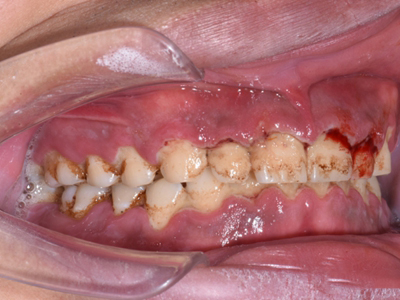

急性坏死性溃疡性龈炎起病急,病程短,常为数天至1-2周,以龈乳头和龈缘的坏死为其特征性损害,尤以下前牙多见,初起时龈乳头充血水肿,个别龈乳头顶端可发生坏死性溃疡,上覆有灰白色坏死物,中央凹下如火山口状。龈缘如虫蚀状,坏死区出现灰褐色假膜,擦去后可见出血创面。龈乳头被破坏后与龈缘成一直线,如刀切状。病损一般不波及附着龈,患处牙龈极易出血,疼痛明显并有腐败性口臭。

重症患者可有低热、疲乏等全身症状,并可伴有下颌下淋巴结肿大和压痛。有的患者可能进展为坏死性龈口炎、坏死性溃疡性牙周炎等疾病,从而导致牙周袋形成、牙槽骨吸收和牙齿松动。

对于急性坏死性溃疡性龈炎,可先轻轻去除局部坏死组织,去除大块龈上牙石,使用过氧化氢溶液擦拭、冲洗和含漱。必要时在清洁后局部涂布抗厌氧菌制剂,全身给予维生素C、蛋白质等支持疗法。重症患者可口服甲硝唑或替硝唑,对于不良诱因要及时去除。急性期过后可采取洁治、刮治以及必要的牙周手术。